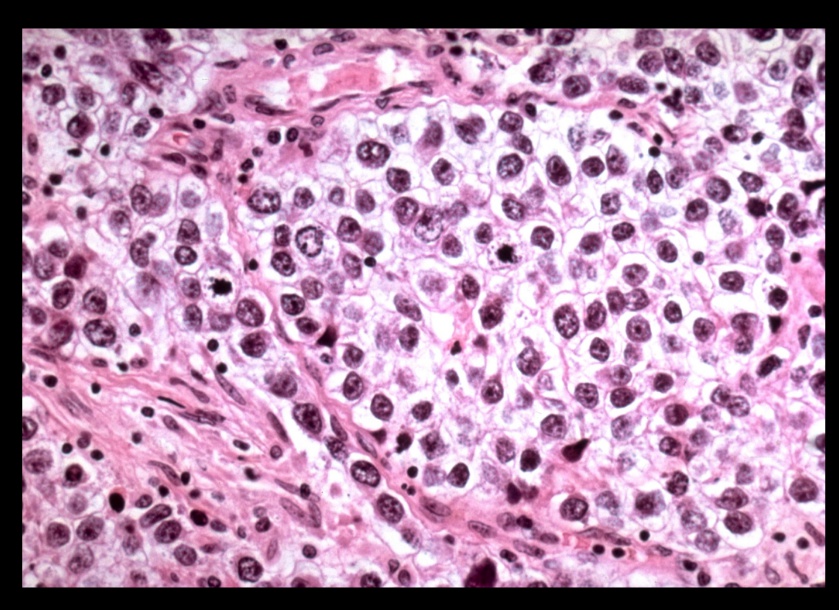

Dysgerminoma

_ Tumor composed of large cells with clear cytoplasm and central nuclei (resemble oocytes)., Dys: bad. Germ: germ cell.

Dysgerminoma. The neoplastic germ cells have clear, glycogen-filled cytoplasm and central nuclei. Fibrous septa containing lymphocytes traverse the tumor.